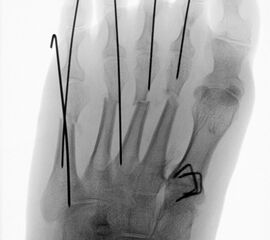

In der minimalinvasiven Fußchirurgie ist es unabdingbar, die Fräse in ihrer Position zum Knochen radiologisch zu kontrollieren, damit vulnerable Wachstumsfugen oder angrenzende Gelenke nicht verletzt werden. Zu diesem Zweck werden mit einem Bildwandler während der Operation die genaue Position der Fräse und der Osteotomieverlauf überprüft, was die Strahlenbelastung im Vergleich zu offenen Verfahren erhöht. Diese Strahlenbelastung hat potenziell einen schädigenden Einfluss auf den noch blutbildenden Knochen von Heranwachsenden. Gesicherte Landmarken am Fuß können die notwendige Zahl der Röntgenbilder und damit die Strahlung minimieren. Ist es erforderlich, mehrere Knochen zu osteotomieren, wie zum Beispiel im Bereich der Kleinzehen, werden anhand der Landmarken kleine Injektionsnadeln auf Höhe der geplanten Osteotomien vorgelegt und radiologisch im Bildwandler (BV) dokumentiert (Abb. 11). Ein solches Bild schafft eine gute Orientierung, sodass auf radiologische Kontrollen intraoperativ weitestgehend verzichtet werden kann.

Abb. 11: Lokalisation mehrerer Stichinzisionen mit einem Röntgenbild.

Zum Lesen der Bildbeschreibung und zur Vollansicht bitte das Bild anklicken. Bild: A. Helmers.